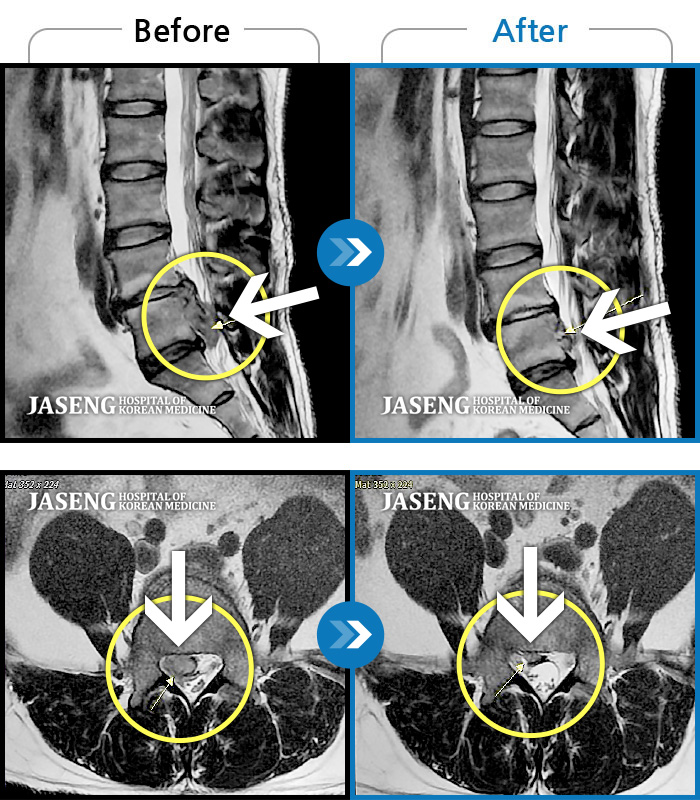

ȯںп Ǹ ǿ ԿǾ, ο ġ ۿ Ƿ ġḦ Ͻñ ٶϴ.